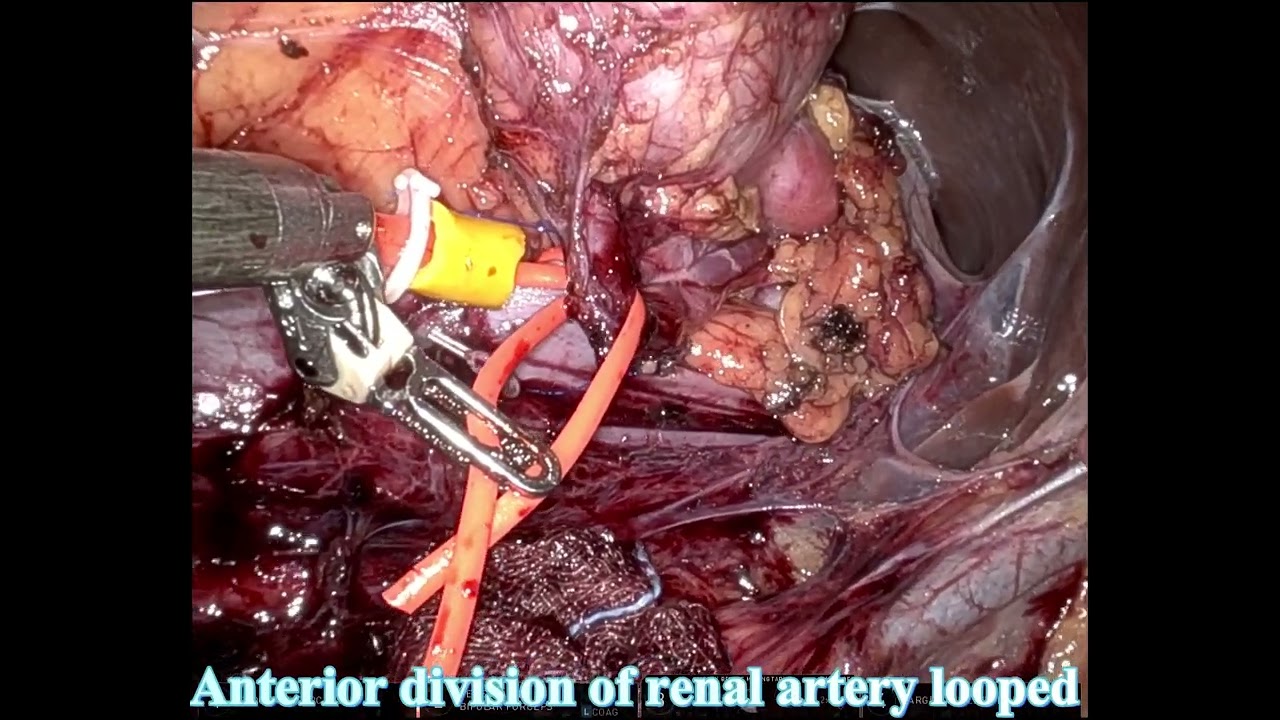

#265 AI-powered real-time annotations during RAPN- Dr. Joan Sureda, Dr. Ketan Badani, Dr. L. Zuluaga